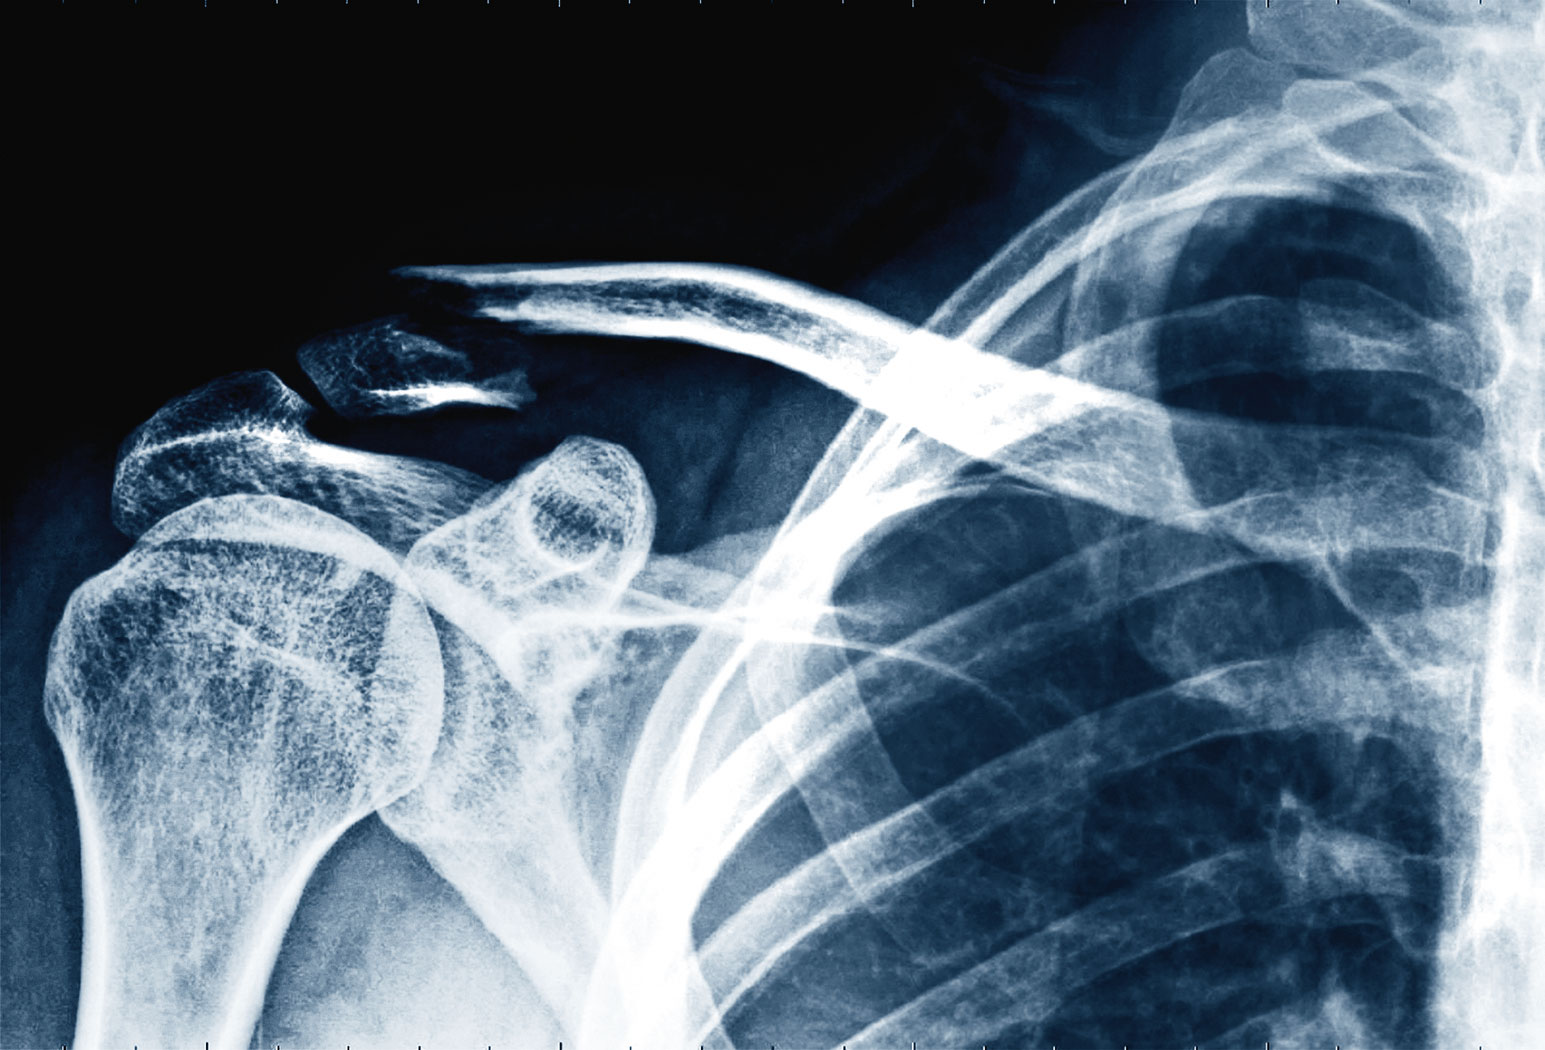

Złamanie kości obojczyka. Złamanie kości obojczyka. materiały prasowe